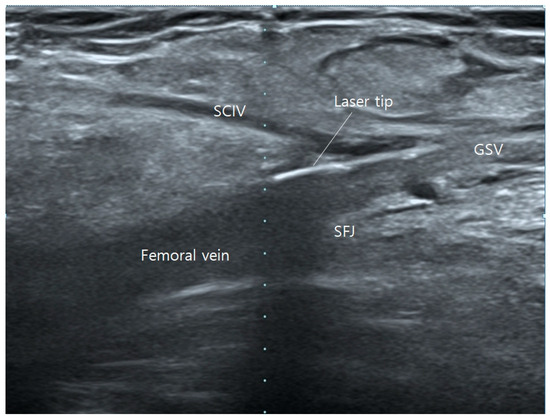

When the superficial epigastric vein (SEV) or the superficial circumflex iliac vein (SCIV) is significantly enlarged with substantial cranial flow causing sacral pain, they are treated concurrently on the day of surgery. Prior to administering tumescent local anesthesia, the EVLA/RFA fiber tip is advanced further into the accessible tributary of either the SEV or SCIV (Figure 2). After the administration of anesthesia, the tributary collapses, making it difficult to advance the tip into the vessel. If the tributaries cannot be accessed during surgery due to vessel angle or small diameter, sclerotherapy can be administered on the day of surgery. This procedure can be performed in upper areas, such as the pelvic region, where tumescent anesthesia is not utilized.

Figure 2. Operative ultrasonography of saphenofemoral junction. Laser tip positioned in superficial circumflex iliac vein (SCIV).